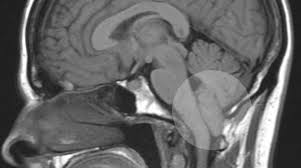

Esta Patología se caracteriza por la presencia de un grupo de defectos

en la estructura del

cerebelo. El cerebelo es la parte del cerebro encargado del

equilibrio. En estas malformaciones, el tejido cerebral se extiende

dentro del canal espinal. Esto puede suceder cuando el cráneo es más

pequeño de lo normal causando que el tejido cerebral sea empujado

hacia abajo. Existen varios tipos de malformaciones de Chiari.